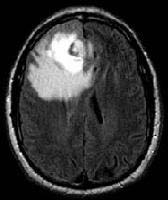

Figure 1: Brain tumour MRI: Magnetic resonance imaging (MRI) of the brain is a safe and painless test that uses a magnetic field and radio waves to produce detailed images of the brain and the brain stem. An MRI scanner consists of a large doughnut-shaped magnet that often has a tunnel in the center. Patients are placed on a table that slides into the tunnel. During the exam, radio waves manipulate the magnetic position of the atoms of the body, which are picked up by a powerful antenna and sent to a computer. The computer performs millions of calculations, resulting in clear, cross-sectional black and white images of the body. These images can be converted into three-dimensional (3-D) pictures of the scanned area. This helps pinpoint problems in the brain and the brain stem when the scan focuses on those areas [3].